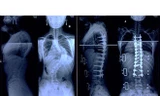

TP - Ngày 6/7, tại Bệnh viện Đa khoa huyện Phong Điền (TP Cần Thơ), gần 1.000 phụ nữ độ tuổi từ 35 đến 53 đến khám sàng lọc, phát hiện sớm bệnh ung thư vú miễn phí.

Đây là hoạt động thuộc dự án phòng chống ung thư vú “Vì phụ nữ, Vì ngày mai” do quỹ Hỗ trợ Bệnh nhân Ung thư - Ngày mai tươi sáng phối hợp Bộ Y tế tổ chức, do tập đoàn Roche tài trợ, khởi động hồi cuối năm 2013.

Dự án nhằm nâng cao nhận thức cho phụ nữ về phòng, chống và điều trị bệnh ung thư vú ở Việt Nam, kéo dài đến 2015. Trước đó, chương trình tổ chức khám cho các chị em ở Hà Nội, Huế và Đà Nẵng.